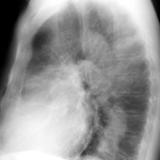

Pulm Stenosis Lat